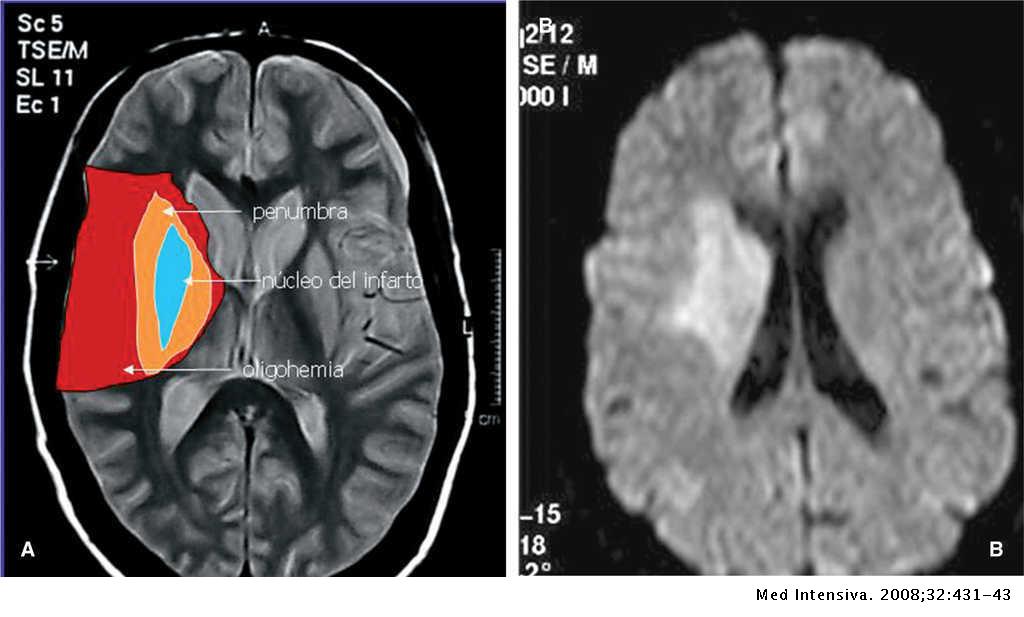

El cerebro depende de la sangre fresca para transportar oxígeno y nutrientes al cerebro y eliminar los productos de desecho. Si una arteria se bloquea, las células del cerebro en la región irrigada por esa arteria dejan de funcionar.

Si la arteria permanece bloqueada durante más de unos minutos, las células cerebrales comienzan a morir. Por eso es fundamental el tratamiento médico inmediato del accidente cerebrovascular.

Cuanto más tiempo no se trata un accidente cerebrovascular, más células cerebrales mueren y más difícil se vuelve la recuperación. Por lo tanto, es fundamental tratar el accidente cerebrovascular rápidamente para preservar la mayor cantidad de tejido cerebral posible.